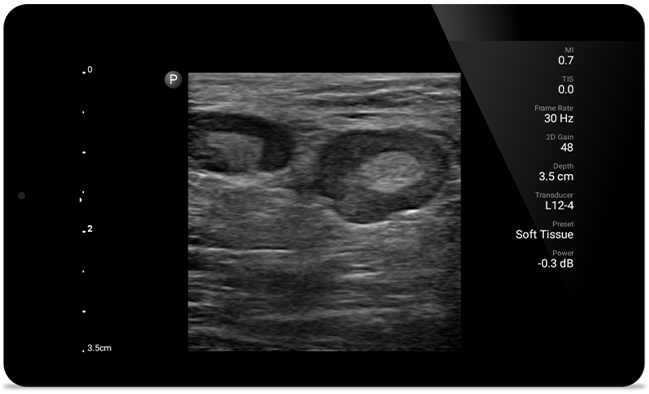

Gebruik de Lumify draagbare echografieoplossing voor musculoskeletale beeldvorming om verwondingen aan de zachte weefsels te detecteren met behulp van HD-beeldvorming van de spieren, gewrichten, ligamenten, pezen en kraakbeen.

Lumify helpt u de fijne details in spieren, gewrichten, ligamenten, pezen en kraakbeen te zien om een nauwkeurigere diagnose te kunnen stellen.

SonoCT versterkt de beeldvorming van het echte weefsel, terwijl willekeurige artefacten worden geëlimineerd. Deze technologie produceert beelden die beter zijn dan conventionele beeldvorming bij tot wel 94% van de patiënten.

Duidelijke beelden van het hele lichaam voor een snelle, nauwkeurige respons tijdens MSK-onderzoeken.

Lumify kan helpen de subtiele details van een beeld zichtbaar te maken en afwijkende weefselstructuren bloot te leggen vanuit verschillende hoeken. Hierdoor kunt u met vertrouwen realtime beslissingen nemen, van diagnose tot herstel.